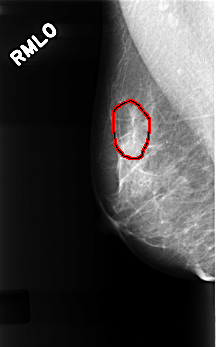

FILE: C_0335_1.RIGHT_MLO.OVERLAY

TOTAL_ABNORMALITIES 1

ABNORMALITY 1

LESION_TYPE CALCIFICATION TYPE FINE_LINEAR_BRANCHING DISTRIBUTION LINEAR

ASSESSMENT 4

SUBTLETY 4

PATHOLOGY BENIGN

TOTAL_OUTLINES 1

BOUNDARY